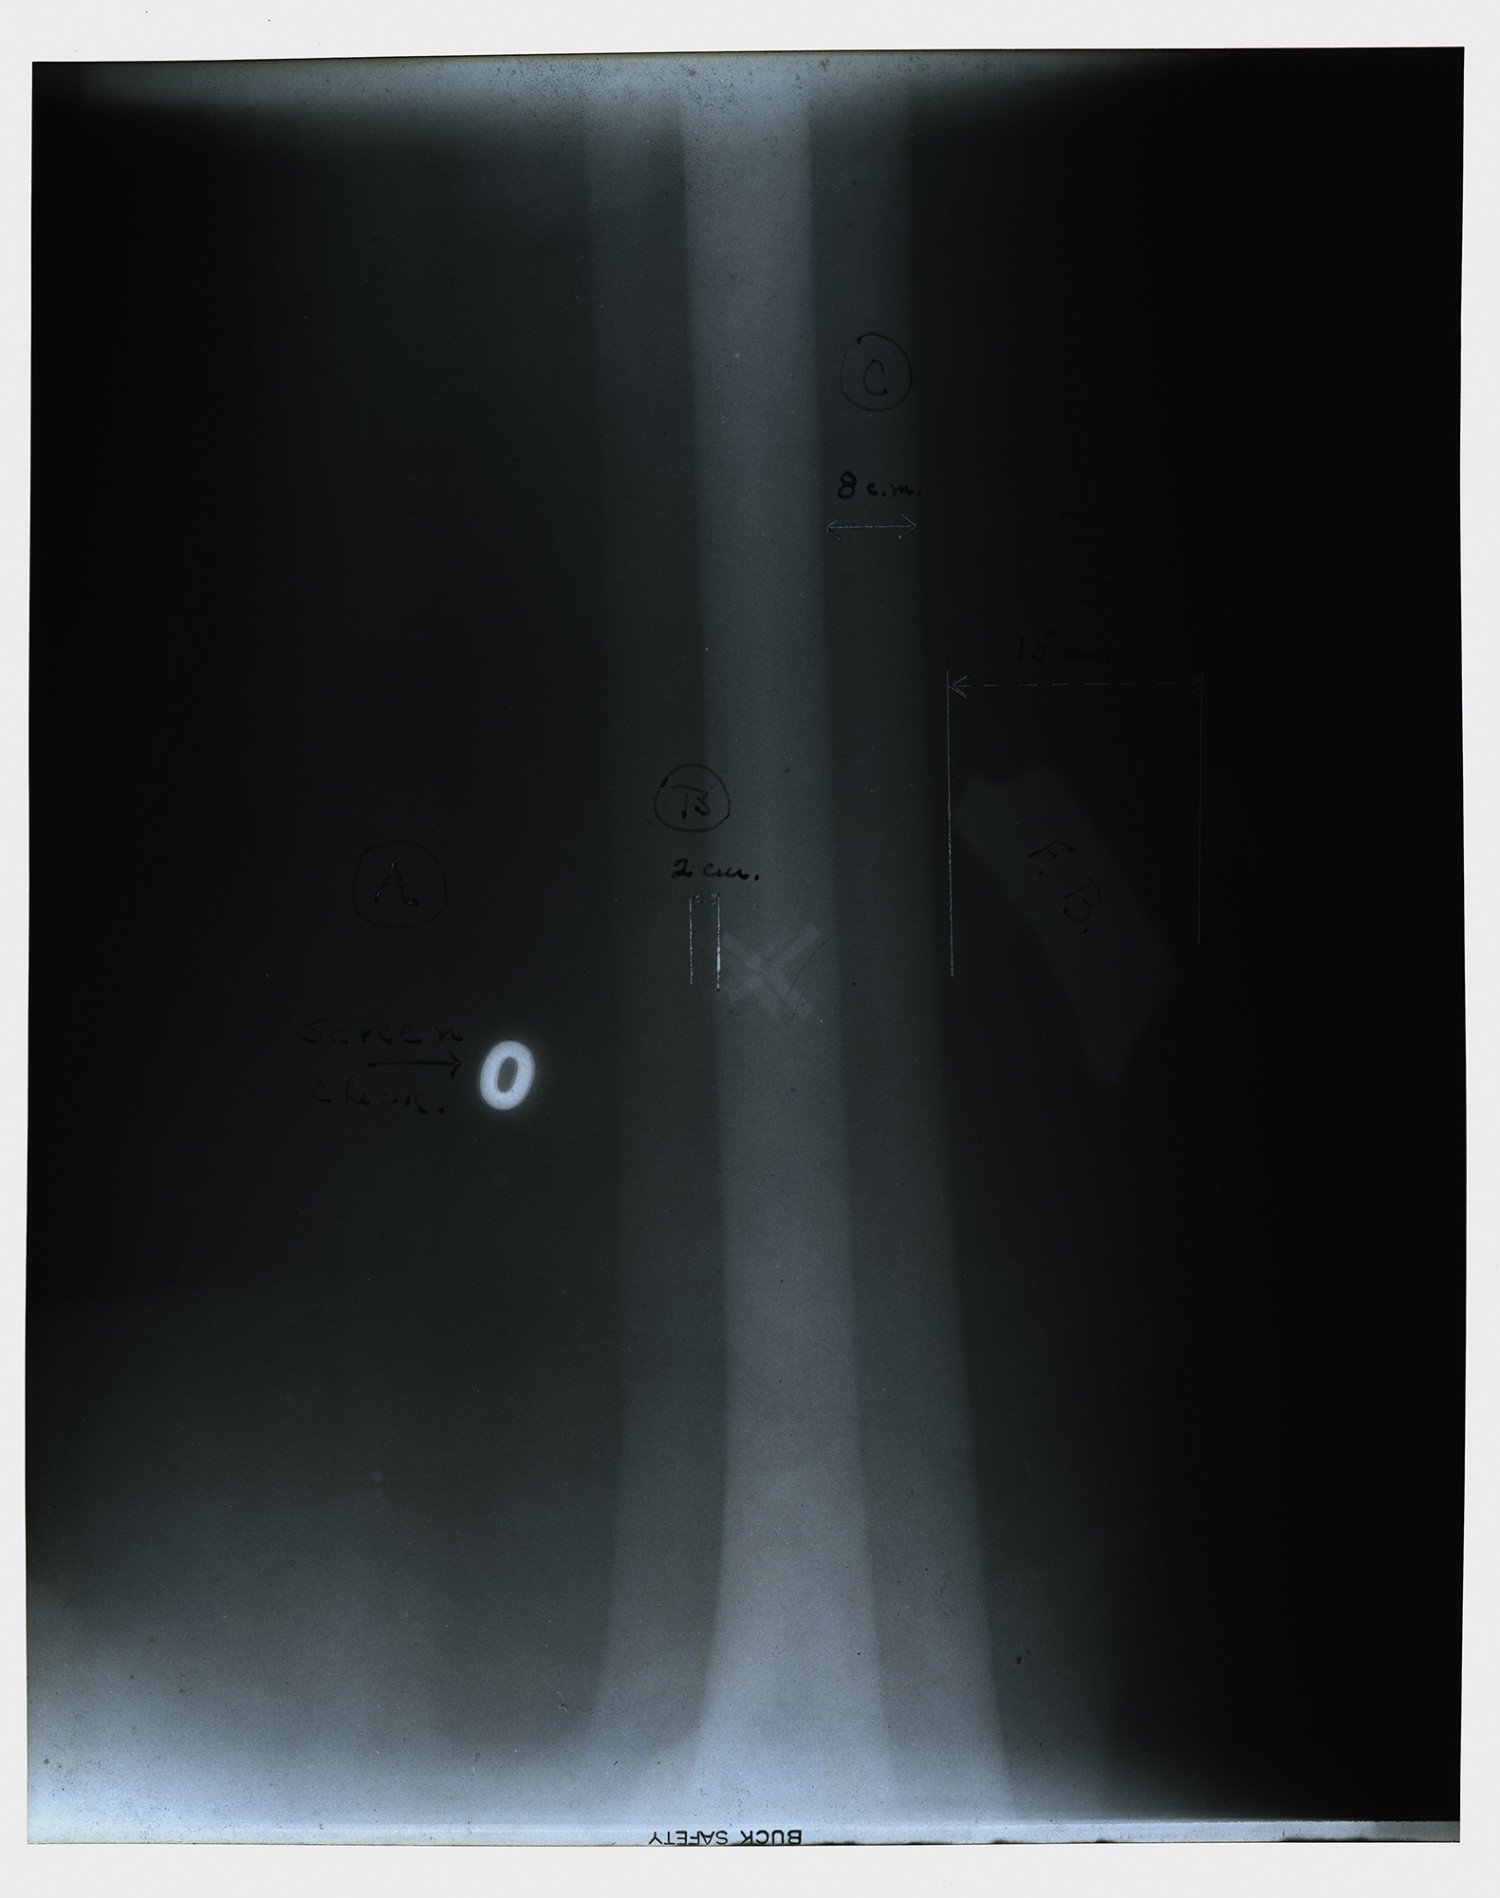

#17303 SHRAPNELL BALL LEFT THORAX. EMPYEMA

LARGE SHRAPNEL DAMAGING ELBOW JOINT

| Description | X-ray taken by Edwin C. Ernst of Base Hospital 21 in Rouen, France. Base hospital 21 was formed from faculty and students from Washington University School of Medicine. Ernst designed his own portable x-ray equipment to help quickly diagnose injured soldiers. |